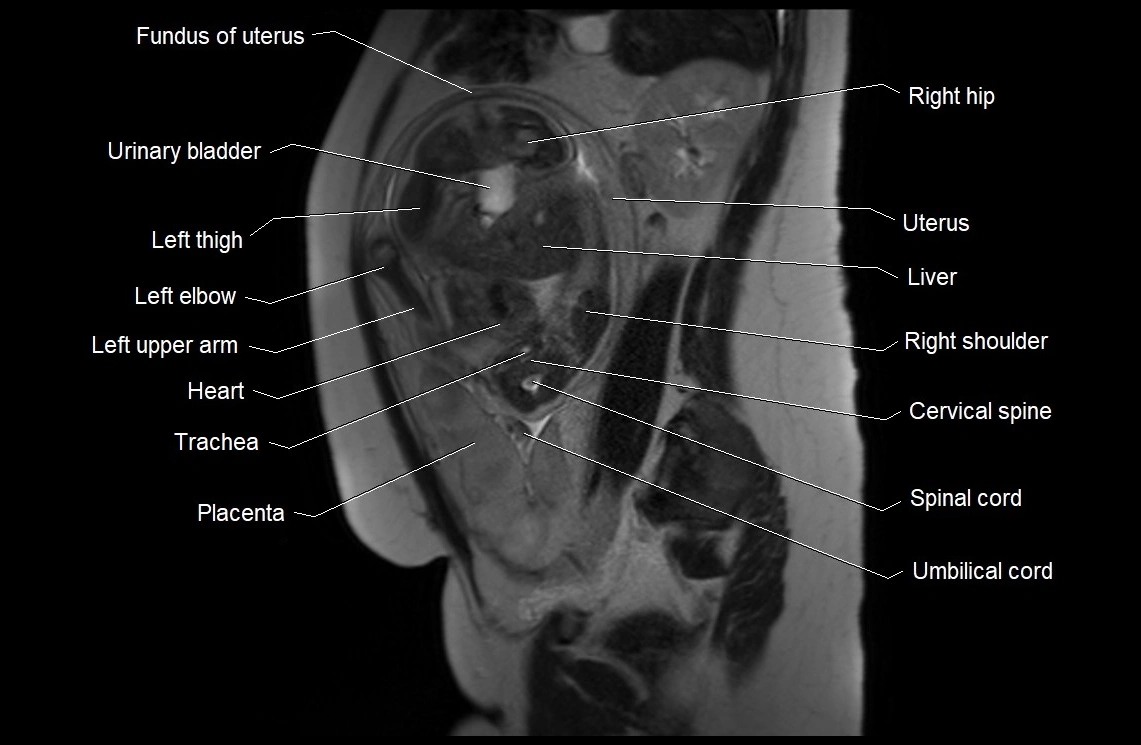

MRI Appearance

T2 HASTE (T2 GRE):

• Amniotic fluid shows very bright hyperintense signal

• Provides natural contrast against fetus and placenta

• Small particles (vernix) may appear as scattered hypointense foci within bright fluid